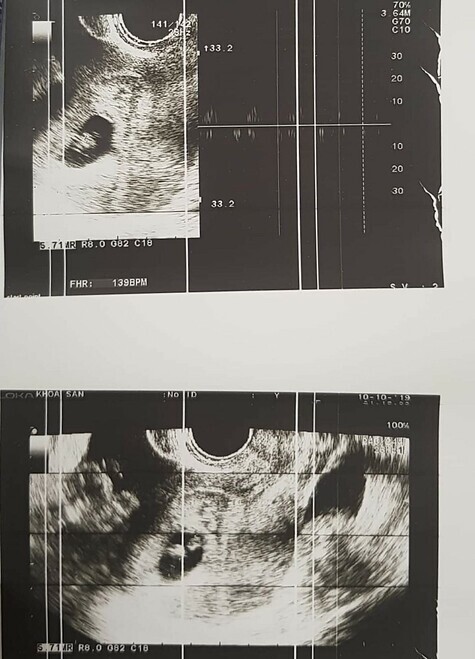

Kết quả siêu âm phát hiện một thai trong buồng tử cung khoảng 7 tuần tuổi, một thai cạnh buồng trứng trái. Bệnh nhân được chẩn đoán mang song thai với một thai trong tử cung và một thai ngoài tử cung đang vỡ, chảy máu.